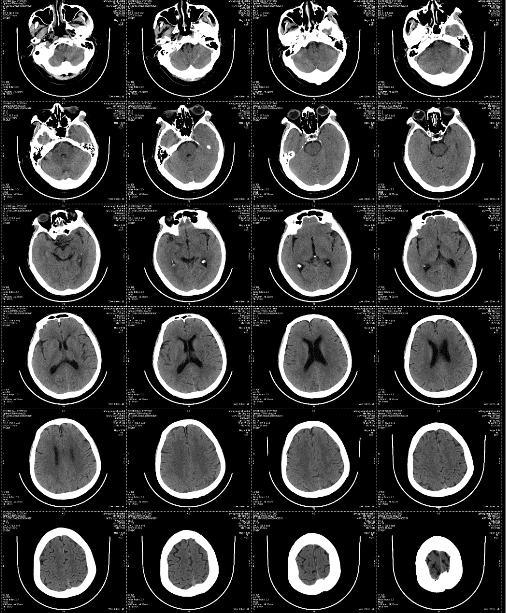

CT影像图

方案介绍

CT影像图,即计算机断层扫描(Computed Tomography,CT)图像,是一种通过X射线对人体进行断层扫描后,经过计算机处理得到的图像。这种图像具有高密度分辨率和密度量化的特点,能够清晰显示人体内部的结构和病变情况。